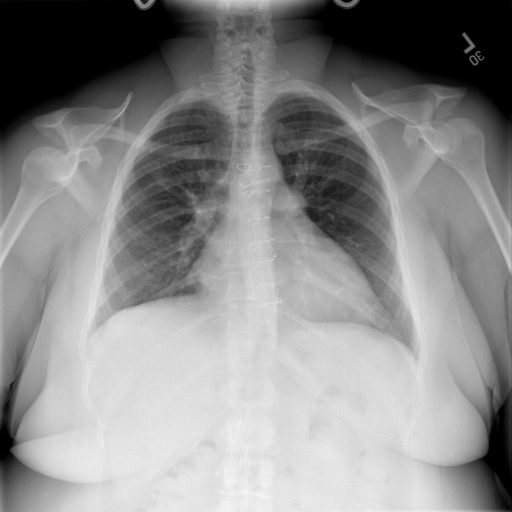

# 本文贡献  - 借助ChatGPT以及公开的数据集,我们构造了一个`X光影像-诊断报告`对的医学多模态数据集; # 数据集 - [MIMIC-CXR](https://physionet.org/content/mimic-cxr-jpg/2.0.0/)是一个公开可用的胸部X光片数据集,包括377,110张图像和227,827个相关报告。 - [OpenI](https://openi.nlm.nih.gov/faq#collection)是一个来自印第安纳大学医院的胸部X光片数据集,包括6,459张图像和3,955个报告。 在上述工作中,报告信息都为非结构化的,不利于科学研究。为了生成合理的医学报告,我们对两个数据集进行了预处理,并最终得到了可以用于训练的**英文报告**。除此之外,为了更好的支持中文社区发展,借助ChatGPT的能力,我们将英文报告进行了中文翻译,并最终形成了可用于训练的数据集。 |数据集|数量|下载链接| |:-|:-|:-| |MIMIC-CXR-zh|-|-| |OpenI-zh|6,423|[诊疗报告](./data/Xray/openi-zh.json) 、[X光影像](https://pan.baidu.com/s/13GBsDMKf6xBZBSHpoWH_EA?pwd=k9sh)| # 快速上手 1. 安装环境 ```bash # 安装依赖 pip install -r requirements.txt # 国内换源安装依赖 pip install -i https://mirrors.aliyun.com/pypi/simple/ -r requirements.txt ``` 此时默认会安装`deepspeed`库(支持`sat`库训练),此库对于模型推理并非必要,同时部分`Windows`环境安装此库时会遇到问题。 如果想绕过`deepspeed`安装,我们可以将命令改为: ```bash # 安装依赖 pip install -i https://mirrors.aliyun.com/pypi/simple/ -r requirements_wo_ds.txt # 安装SwissArmyTransformer pip install -i https://mirrors.aliyun.com/pypi/simple/ --no-deps "SwissArmyTransformer>=0.3.6" ``` 2. 模型推理 CLI推理: ```python python cli_demo.py --from_pretrained checkpoints/finetune-XrayGLM-05-25-01-04 --prompt_zh '详细描述这张X光影像' ``` 更多[参数](https://github.com/WangRongsheng/XrayGLM/blob/main/cli_demo.py#L16) # 效果展示 |X光影像|诊疗报告(医生)|XrayGLM| |:-|:-|:-| ||根据X射线图像,心脏大小正常,肺部看起来很清晰。已经排除了肺炎、积液、水肿、气胸、腺病、结节或肿块的存在。该发现表明一切正常。换句话说,总体印象是胸部正常。|X光片显示,心脏大小正常。肺部没有气胸或胸腔积液的证据。骨骼结构看起来没有任何异常。总的来说,X光片表明没有发现急性心肺疾病的迹象。| ||X光图片显示没有扭曲的区域、可疑的骨质不透明度或胸腺积液。心脏大小轻微增大,但非常稳定。此外,没有气胸的证据,肺野也正常。总体来说,X光片显示没有急性心脏异常,但要注意轻微的心脏扩大。|X光片显示,心脏大小正常。肺部和纵隔轮廓清晰,没有气胸或胸腔积液的证据。骨骼结构完整,没有任何急性异常。| ||心影形态在正常范围内。没有急性骨质异常。有可能出现没有明显的吸水或肺实质状况的线索。没有大面积积液或气胸。有可能怀疑其有误吸或肺实质问题。为了确诊和治疗,可能需要进行适当的影像学随访。|心脏大小正常,肺部和纵隔轮廓清晰。没有急性异常或活动受限的证据。没有任何明显的气胸、胸腔积液或肺不张的迹象。此外,也没有发现任何局灶性骨质异常或其他急性疾病。| # 项目致谢 1. [VisualGLM-6B](https://github.com/THUDM/VisualGLM-6B)为我们提供了基础的代码参考和实现; 2. [MiniGPT-4](https://github.com/Vision-CAIR/MiniGPT-4)为我们这个项目提供了研发思路; 3. ChatGPT生成了高质量的中文版X光检查报告以支持XrayGLM训练; 4. [gpt_academic](https://github.com/binary-husky/gpt_academic)为文档翻译提供了多线程加速; 5. [MedCLIP](https://github.com/RyanWangZf/MedCLIP) 、[BLIP2](https://huggingface.co/docs/transformers/main/model_doc/blip-2) 、[XrayGPT](https://github.com/mbzuai-oryx/XrayGPT) 等工作也有重大的参考意义;  这项工作由[澳门理工大学应用科学学院](https://www.mpu.edu.mo/esca/zh/index.php)硕士生[王荣胜](https://github.com/WangRongsheng) 、[段耀菲](https://github.com/IsBaSO4) 、[李俊蓉](https://github.com/lijunrong0815)完成,同时这项工作受到[檀韬](https://scholar.google.com/citations?hl=zh-CN&user=lLg3WRkAAAAJ)副教授、[彭祥佑](http://www.patrickpang.net/)老师的帮助支持。 *特别鸣谢:[USTC-PhD Yongle Luo](https://github.com/kaixindelele) 提供了有3000美金的OpenAI账号,帮助我们完成大量的X光报告翻译工作 # 免责声明 本项目相关资源仅供学术研究之用,严禁用于商业用途。使用涉及第三方代码的部分时,请严格遵循相应的开源协议。模型生成的内容受模型计算、随机性和量化精度损失等因素影响,本项目无法对其准确性作出保证。即使本项目模型输出符合医学事实,也不能被用作实际医学诊断的依据。对于模型输出的任何内容,本项目不承担任何法律责任,亦不对因使用相关资源和输出结果而可能产生的任何损失承担责任。 # 项目引用 如果你使用了本项目的模型,数据或者代码,请声明引用: ```bash @misc{wang2023XrayGLM, title={XrayGLM: The first Chinese Medical Multimodal Model that Chest Radiographs Summarization}, author={Rongsheng Wang, Yaofei Duan, Junrong Li, Patrick Pang and Tao Tan}, year={2023}, publisher = {GitHub}, journal = {GitHub repository}, howpublished = {\url{https://github.com/WangRongsheng/XrayGLM}}, } ``` # 使用许可 此存储库遵循[CC BY-NC-SA](https://creativecommons.org/licenses/by-nc-sa/4.0/) ,请参阅许可条款。